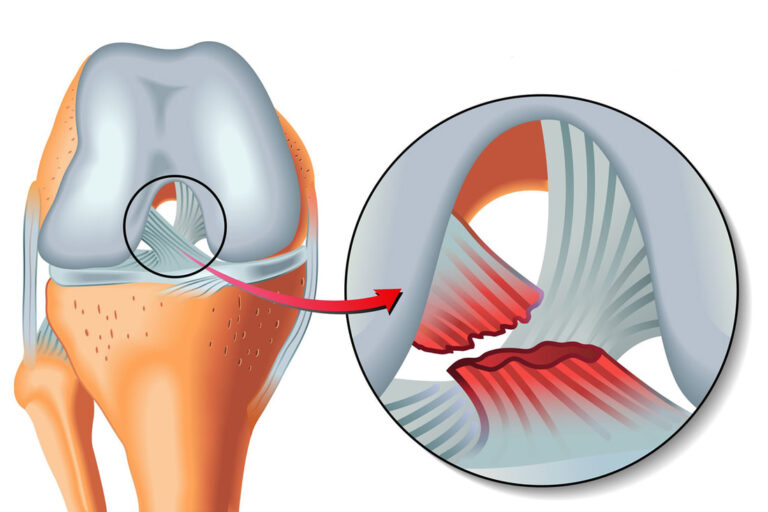

- Traumatismes ligamentaires : entorses, ruptures partielles ou complètes (genou, cheville, épaule…).

- Micro-lésions du cartilage : souvent silencieuses au début mais responsables de douleurs à l’effort.